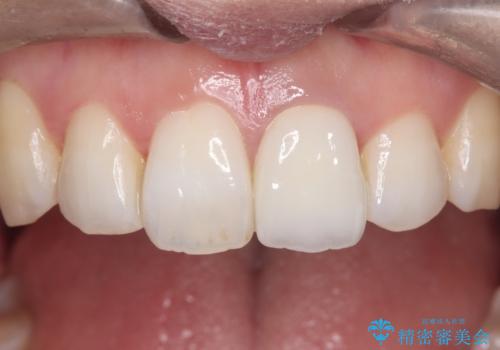

繰り返すプラスチックの欠けを解消。広範囲の修復に適したセラミッククラウン

担当医 河口智英